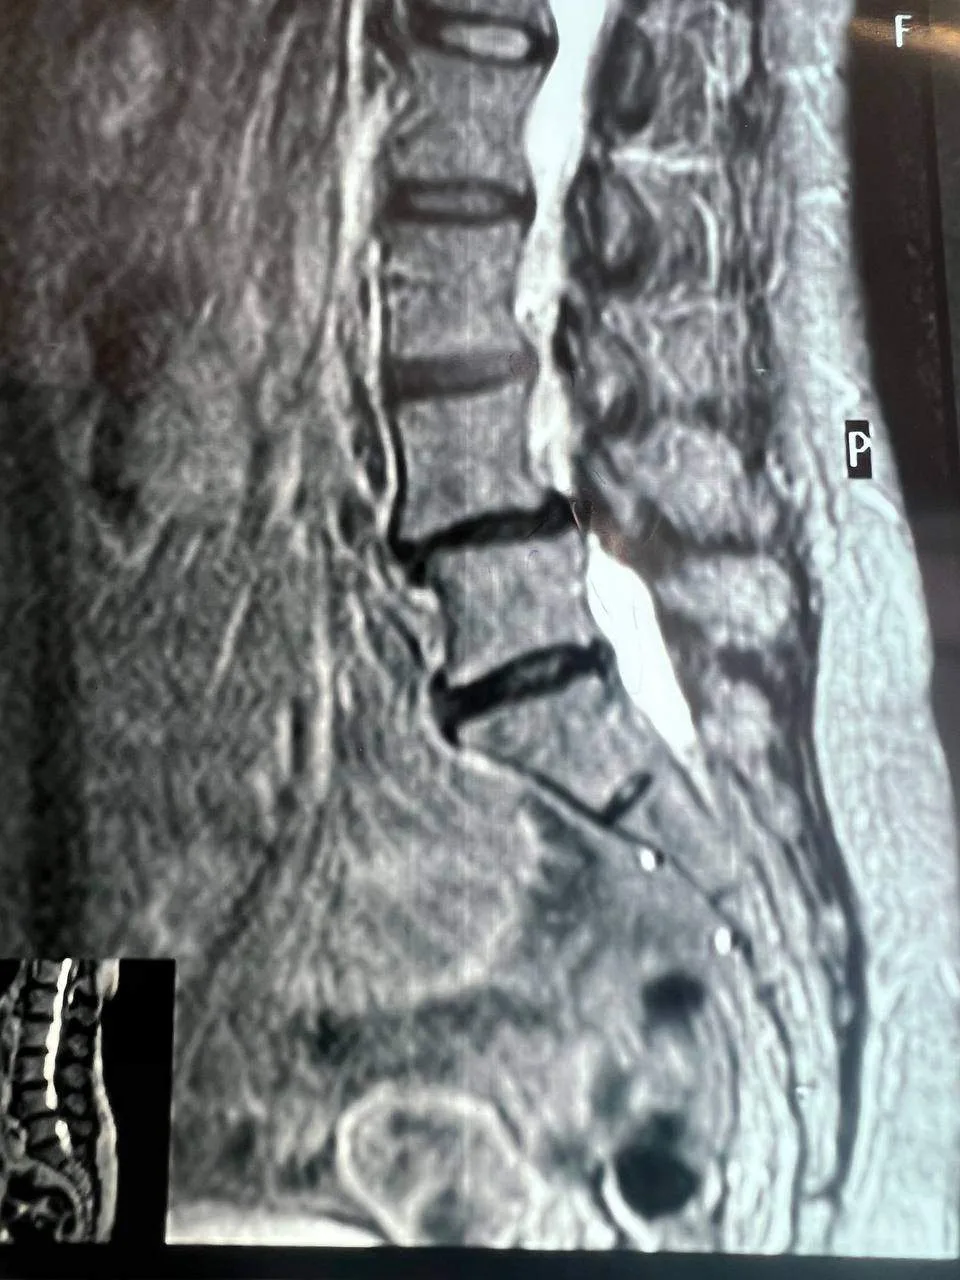

Обследование показало сразу несколько проблем, включая поражение межпозвоночных дисков и комбинированный стеноз позвоночного канала на уровне четвертого и пятого поясничных позвонков.

До госпитализации пациентка в течение года проходила несколько курсов консервативной терапии, однако улучшений это не принесло. В последние месяцы боль усилилась, а расстояние, которое она могла пройти, заметно сократилось. В стационаре ей предложили провести декомпрессивно-стабилизирующую операцию.

Во время хирургического вмешательства врачи устранили сдавливание с двух сторон, удалили грыжу и заменили поврежденные диски имплантами. Используя микрохирургическую технику, оптический прибор и специальный инструментарий, специалисты ликвидировали компрессию дурального мешка и сегментарных нервов. Кроме того, медики исправили смещение позвонка. Для стабилизации позвоночника установили конструкцию из четырех титановых винтов и двух балок.